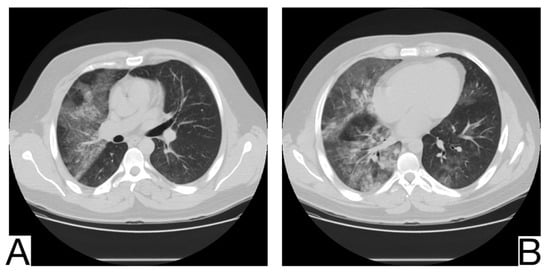

Viral pneumonia is defined as a diverse entity, and it is mainly the current epidemic context that suggests the origin of COVID-19. The treatment proved to be similar at present []. Radiological characteristics in differential diagnosis: preferential central-parenchymal involvement (Influenza type A, Adenovirus, Hantavirus) (Figure 6A); additional findings, such as centrolobular nodules and bronchial wall thickening (RSV, MERS, Influenza type A); coexisting pulmonary edema (Hantavirus); pleural effusions (RSV, MERS); hilomediastinal lymphadenomegaly (Influenzae type A) [,,].

Figure 6. (A). Multifocal areas of poorly defined focal consolidation in a patient positive for influenza A (H1N1) (B). Bilateral ground-glass opacities and dense airspace consolidations in a patient with Pneumocystis jirovecii pneumonia (C). Halo sign in a patient with aspergillosis. Note. Adapted from Elmokadem et al. (2021) [] (A), Sullivan et al. [] (2020) (B), and Dr. Laughlin Dawes (C).

10.3. Pneumocystis Pneumonia

Pneumocystis pneumonia is an opportunistic fungal infection that mainly affects immunodeficient patients affected by AIDS or undergoing immunosuppressive therapy (Figure 6B) []. History and laboratory tests are helpful but often insufficient for a differential diagnosis of COVID-19 pneumonia [,,].

Imagistic diagnosis characteristics are symmetrical, centroparenchymal and perihilar, ground-glass, confluent opacities, generally with subpleural reduction, a predilection for the upper lobes, sometimes cobblestone appearance; pneumatoceles [,].

10.4. Aspergillosis

It is caused by Aspergillus Fumigatus and generally affects immunocompromised patients with severe neutropenia. Radiological diagnosis highlights: ground glass opacities and cobblestone aspect are not typical and do not precede condensations, which frequently show a surrounding halo of ground glass (halo sign) [] (Figure 6C).

In case of consolidations without ground glass halo and the absence of other ground glass opacities, COVID-19 pneumonia is unlikely; lymphadenopathy and pleural effusions are also present.